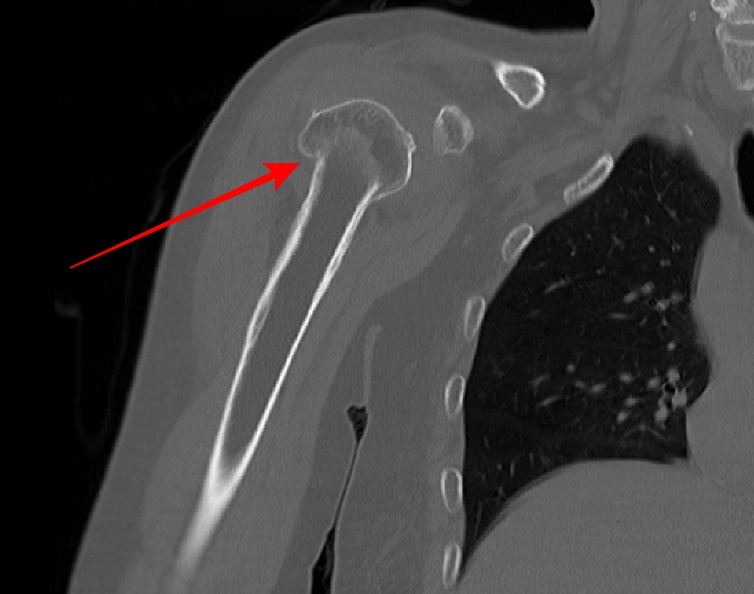

2022.06.04 CT SCAN

- F/50대

- 어제 넘어짐

-velpeau bandage 상태

- Rt Shoulder CT

- surgical neck Fx 의심 되어 검사 의뢰됨.

- 오른쪽 어깨에 velpeau bandage를 한 상태로 통증이 있는 상태였다.

- shoulder 전체를 포함하여 scan 하였다.

- axial 영상을 획득 후 MPR로 재구성하였다.

- 붉은색 화살표가 골절된 부위다.

displaced neck fracture of humerus with impaciton

입원 후 수술예정이다.